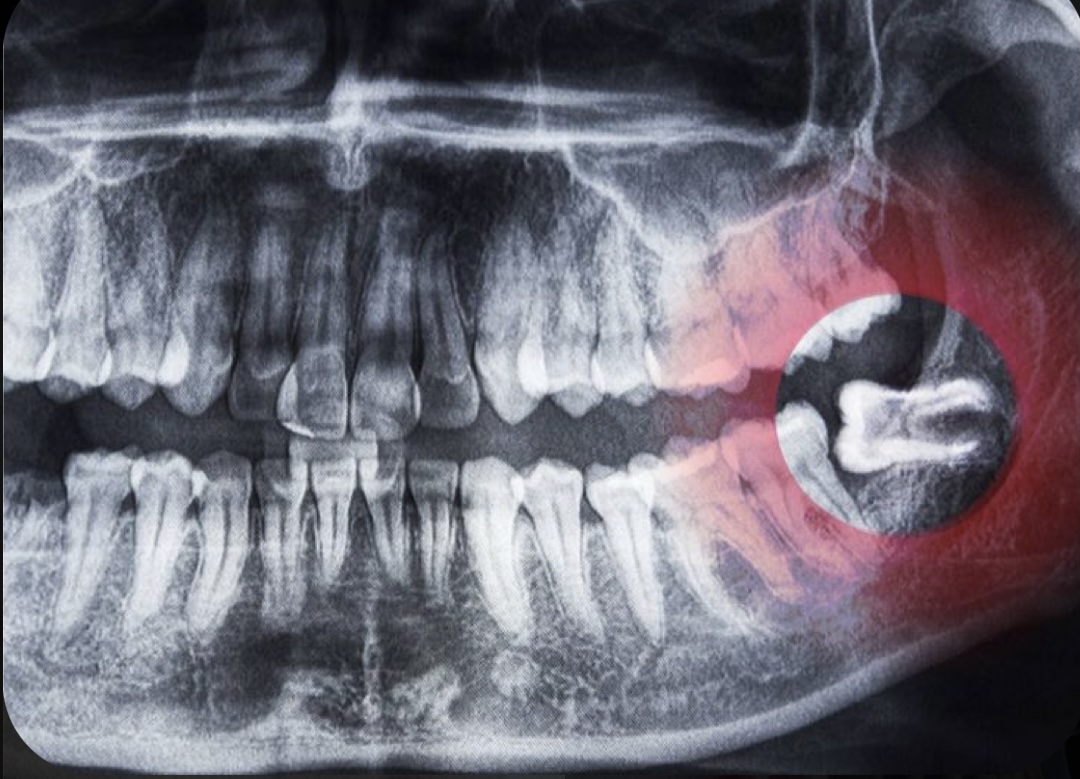

No siempre, dependerá de: si están sin patología (sin caries), en oclusión y funcionales no es necesario. Se extraen en el caso que no exista suficiente espacio para erupcionar sin mantener capuchón mucoso que lo puede cubrir total o parcialmente y generar molestias asociadas de manera periódica lo que se conoce como pericoronaritis. O si existen lesiones quísticas asociadas por falta de espacio para erupcionar (quiste paradental) u otras lesiones asociados quiste folicular etc.

Si están en malposición y en vez de salir normalmente están en 90 grados e impactan contra el 2 molar puede favorecer la aparición de caries o reabsorciones radiculares de los dientes contiguos.